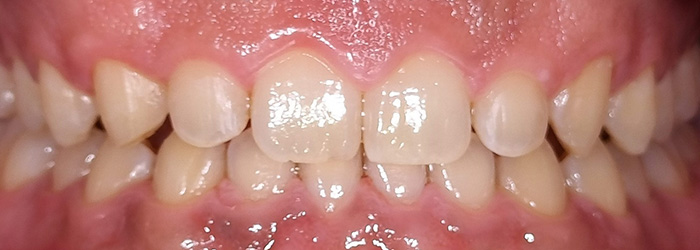

前歯の見た目と噛み合わせのバランスを整えたケース

「前歯が強くかみ込んでいる気がする」「歯並びだけでなく、噛み合わせも気になる」

このようなお悩みでご相談いただくことがあります。

今回の患者様は、ディープバイト(過蓋咬合)による前歯の見た目と噛み合わせを気にされて来院されました。ディープバイトとは、上の前歯が下の前歯に深く重なっている噛み合わせのことで、見た目の問題だけでなく、前歯や顎への負担につながることがあります。

本症例では、マウスピース型矯正装置(インビザライン)を用いて治療を行いました。合計84枚のアライナーを使用し、歯並びだけでなく咬合の深さにも配慮しながら治療を進めました。

治療後は、前歯の見た目のバランスが整い、噛み合わせも改善しました。

当院では、見た目を整えるだけではなく、治療後の噛み合わせまで考慮した矯正治療を大切にしています。